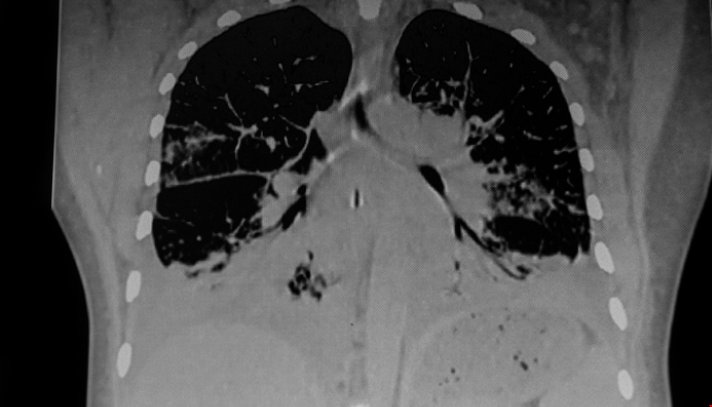

一個耗資940萬英鎊的合作研究中心,包括來自諾丁漢大學的研究人員,將加速改進測試、治療和潛在的治愈數千名患有罕見呼吸系統疾病(肺病疾病)的人,據悉,LifeArc罕見呼吸系統疾病中心將把兒童、成人和家庭與臨床專家、研究人員、投資者和行業領袖聯系起來。該中心的專家將進行合作,旨在克服一些阻礙罕見疾病患者獲得新的檢測和治療方法的障礙。下面就隨tops留學老師一起來看看吧!

據悉,全球有3億多人患有罕見疾病,其中每20人中就有1人與呼吸系統疾病有關。雖然它們本身很罕見,但它們共同造成了巨大的社會和經濟成本。

這項合作將建立一個全英國范圍的匿名組織樣本和疾病模型庫,使研究人員能夠推進開創性的治療方法。它將努力降低罕見呼吸道疾病研究投資的風險,建立罕見病患者臨床試驗所需的伙伴關系和創新基礎設施。該中心團隊還旨在提高公眾對患有罕見呼吸系統疾病的現實生活的認識,并提高患者對可以改善其生活質量的資源的認識。